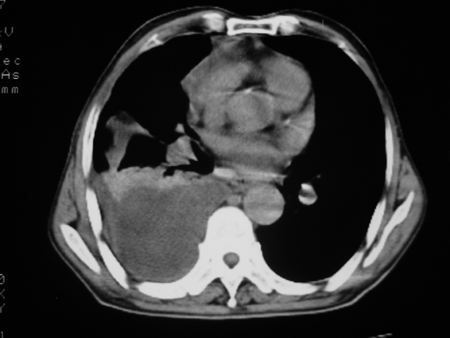

男77岁,胸痛就诊

右侧胸腔积液,部分包裹,右下肺膨胀不全,右下肺感染。

考虑右肺门占位并下叶不张 右胸包裹积液

右肺中叶及下叶炎症并胸腔积液(部分包裹),建议抽液后复查ct除外占位。